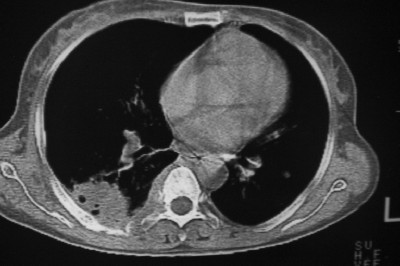

以下是引用天南地北在2007-4-10 1:49:00的发言:[br]考虑右下叶周围型肺癌伴肋骨转移。

以下是引用jone-baby在2007-4-10 8:45:00的发言:[br][br] [br] 患者[br]有发热史,x线片考虑肺脓肿.肺脓肿可以导致肋骨破坏吗?[br]脓肿可以排除吗? [br] [br] [br]

以下是引用林建春在2007-4-10 7:35:00的发言:[br]周围型肺癌侵犯肋骨

以下是引用liuyue在2007-4-10 7:56:00的发言:[br]周围型肺癌侵犯肋骨,左肺转移。

以下是引用zhangzhongshou在2007-4-10 10:24:00的发言:[br]右肺下叶背段厚壁空洞,伴胸膜改变、肋骨破坏,其内可见死骨、周围骨质硬化,左肺可见小结节影,[br]单纯影像学更支持结核。建议进一步检查。